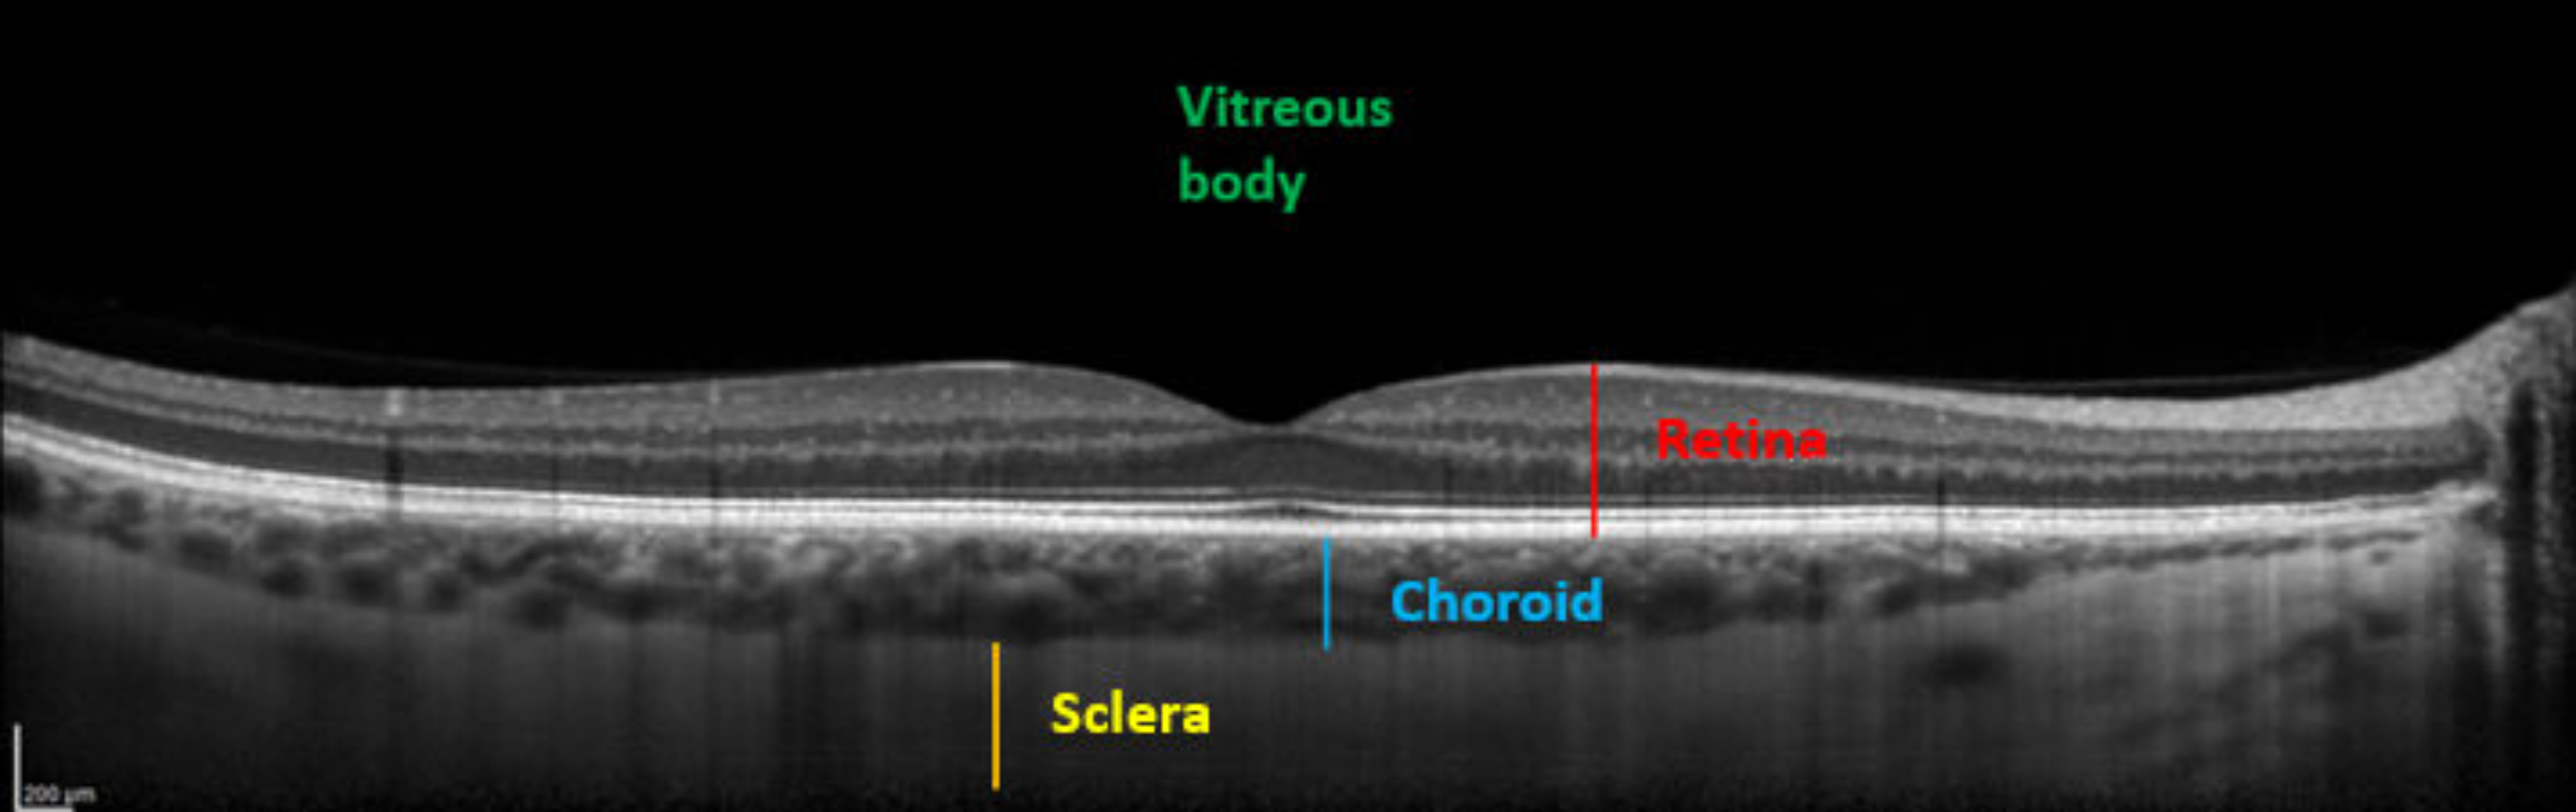

2.2.1. Ophthalmic Measurements

5.1. Subfoveal Choroidal Thickness

| SFCT (%) | 100 | 96.6 (±13.89) | 0.016 | 98.4 (±5.7) | 0.21 (ns) |

| SFCT (µm) | 327.1 (±102.0) | 318.1 (±109.7) | 0.0326 | 322.2 (±102.1) | 0.2434 |